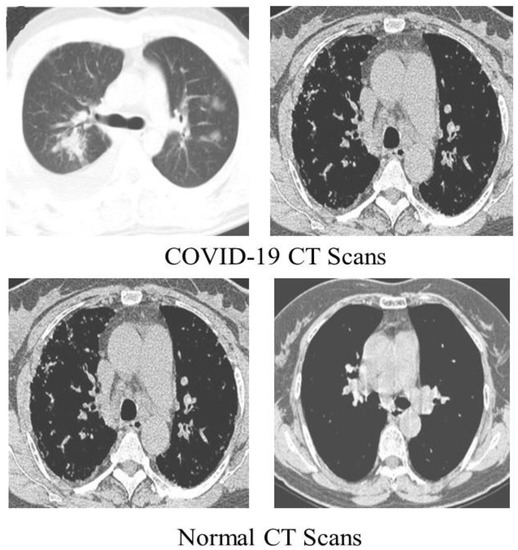

We detected COVID-19 by utilizing CT scans from a freely accessible SARS-CoV-2 CT scan dataset [44] comprising 1252 CT scans of COVID-19 patients, with 1230 CT scans of normal people (total of 2482 CT scans). These statistics were gathered from real patients in Brazilian hospitals. Figure 4 displays a few examples from the dataset.

Figure 4.

COVID-19 (first row) Normal CT scan (second row) samples of the dataset.